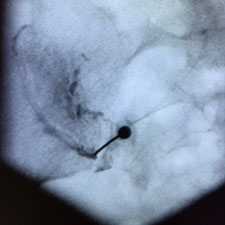

La infiltració del múscul piramidal és una patologia freqüent pel que fa al dolor de la natja irradiat cap a l'extremitat inferior.